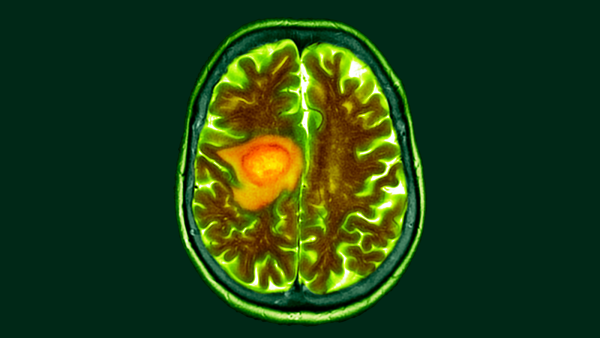

When formulating mRNA vaccines for individuals with brain cancers in 2016, our group, steered by pediatric oncologist Elias Sayour, came upon that mRNA can educate immune systems to eradicate cancers — even if the mRNA is unrelated to malignancy.

To comprehend the fundamental mechanism, we consulted animal prototypes. We detected that COVID-19 mRNA vaccines function akin to a warning signal, activating the body’s immune system to recognize and wipe out tumor cells and conquer the cancer’s capability to turn off immune cells. When integrated, vaccines and immune checkpoint inhibitors collaborate to unleash the full force of the immune system to eliminate cancer cells.